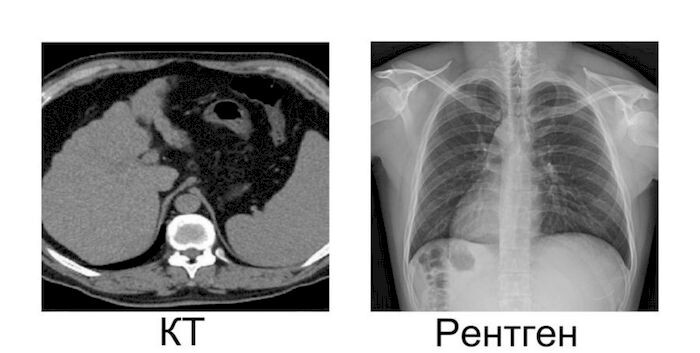

Между врачами ходит молва – чем раньше болезнь выявить, тем легче ее лечить. К коронавирусной инфекции это также относится. Отвечая на вопрос, что эффективнее при выявлении этого заболевания, здесь можно смело сказать, что компьютерный томограф.

Коронавирусная инфекция имеет симптом «матового стекла», который не видно при проведении рентгена.

Отличается компьютерный томограф от рентгена своей надежностью и большей точностью в определении диагноза. Популяризация этого метода исследования произошла по причине создания изображения в 3D формате, это говорит о том, что врач не упустит ни одной детали и заметит все отклонения от нормы.

Чаще всего рентген лёгких делается в профилактических целях, а если речь заходит о каком-либо заболевании, то компьютерная томография – идеальный вариант. Именно при проведении КТ можно наблюдать состояние ткани на любом уровне, сразу возможно заметить образование даже небольшого количества инфильтрата и установить степень поражения лёгких.